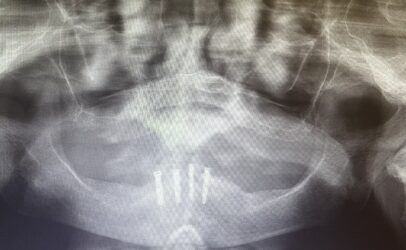

I have a question about restoring this case. The plan was to do over denture. But now the patient can’t handle the denture and she wants a bridge. Implants are fully healed and ready to be restored. She doesn’t want to wait another 5 months ( so adding 2 posterior implants is not an option). How would you go about restoring this? Screw…

Read more

• I typically try not to cantilever more than one tooth. In this case you may be able to get away with two smaller teeth and get to the 2 pre molar if placing more posterior implants aren’t an option.